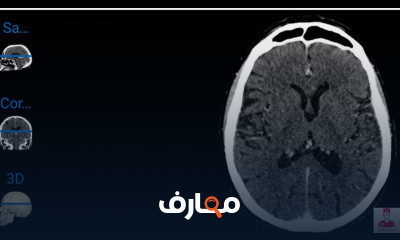

دورة تشريح إشعاعي تهدف إلى تعريف الطلاب بكيفية دراسة تراكيب الجسم البشري باستخدام وسائل التصوير الطبي المختلفة مثل الأشعة السينية، الأشعة المقطعية (CT)، التصوير بالرنين المغناطيسي (MRI)، والموجات فوق الصوتية. يركز كورس تشريح إشعاعي على فهم العلاقات التشريحية بين الأعضاء والعظام والأنسجة كما تظهر في الصور الإشعاعية، مع مقارنتها بالتشريح التقليدي لتعزيز دقة التشخيص. يتعلم الطالب كيفية التعرف على المعالم التشريحية في الصور المقطعية والمستويات المختلفة للجسم، والتفريق بين الوضع الطبيعي والمرضي. كما تتناول الدورة تطبيقات سريرية مهمة مثل تشخيص الكسور، الأورام، أمراض القلب والرئة والجهاز العصبي. يتم دمج الجانب النظري مع التمارين العملية باستخدام صور شعاعية حقيقية ونماذج ثلاثية الأبعاد. الدورة أساسية لطلاب الطب والأشعة والعلاج الطبيعي، حيث تمنحهم القدرة على قراءة الصور التشخيصية وفهم البنية الداخلية للجسم بشكل دقيق يساعد في ربط التشريح بالممارسة السريرية,الدورة مجانية وبشهادة معتمدة. المختصر المفيد Radiological anatomy